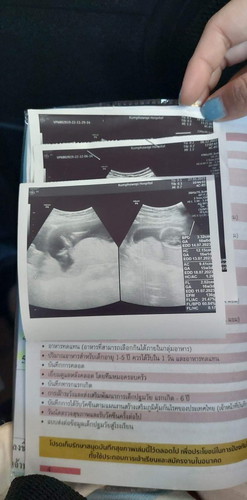

รูปแรกเหมือนจะเป็นส่วนลำตัวกับขาน้อง อีกรูปเป็นขนาดรอบศีรษะน้อง